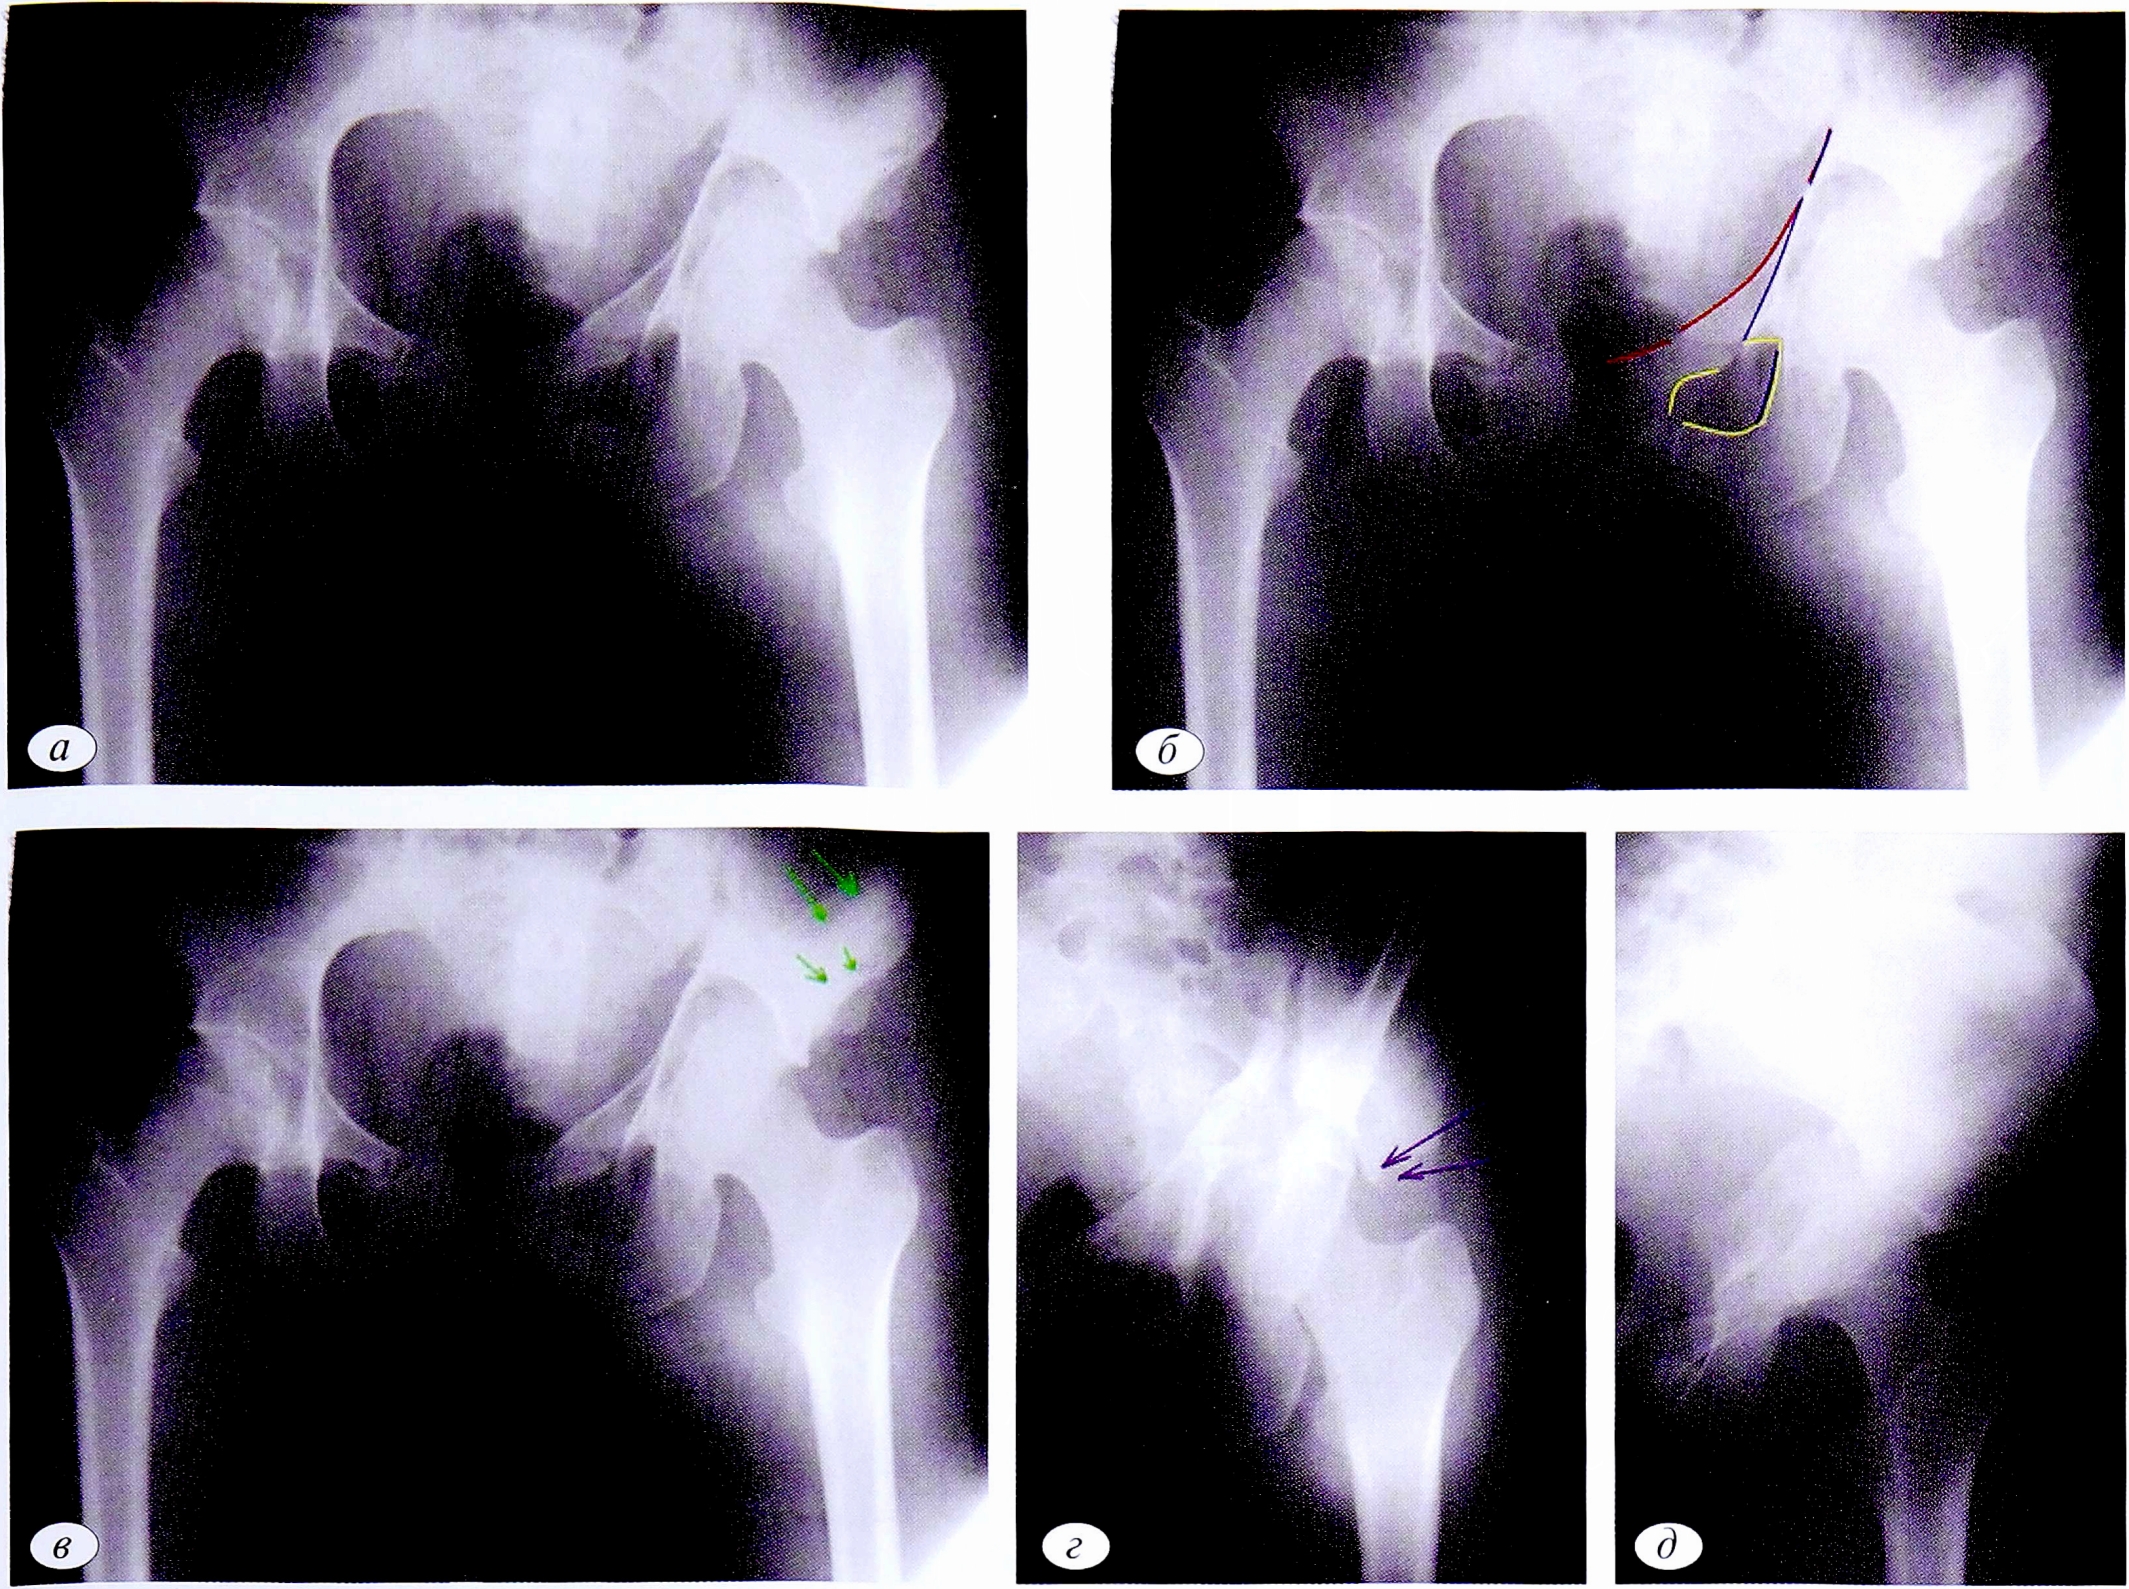

Наблюдение №4

В клиническом наблюдении на обзорной рентгенограмме таза также определяется повреждение 3 линий (подвздошно-гребешковая, подвздошно-седалищная линии, контуры запирательного отверстия), которое характерно для повреждения обеих колонн вертлужной впадины (рис. 4, а). Это позволяет на первом этапе исключить все простые типы переломов, а также 2 типа ассоциированных переломов: задней колонны, ассоциированного с переломом задней стенки, а также поперечного, ассоциированного с переломом задней стенки (см. рис. 4, б).

При дальнейшем анализе обзорной рентгенограммы можно выявить дополнительную плоскость перелома, проходящую через крыло подвздошной кости (см. рис. 4, в). Эта рентгенологическая особенность свидетельствует о наличии фрагмента передней колонны. При Т-образном переломе такой фрагмент отсутствует и, следовательно, этот тип повреждения также исключается.

Для дифференциальной диагностики оставшихся 2 типов переломов необходимо выполнение прицельной рентгенографии в запирательной проекции. В этом клиническом примере (рис. 4, г) определяется положительный симптом шпоры. Рентгенологически этот симптом обусловлен выведением контура заднего отдела подвздошной кости, который не имеет связи с суставной поверхностью (стрелка на рентгенограмме). Таким образом, методом исключения диагностирован двухколонный перелом вертлужной впадины.

Рентгенограмма в подвздошной проекции в случае двухколонного перелома позволяет подтвердить факт повреждения обеих колонн вертлужной впадины, но не дает возможность провести дифференциальную диагностику между двухколонным переломом и переломом передней колонны, ассоциированным с задним полупоперечным переломом (см. рис. 4, д).

Рис. 4. Пациент №4. а — обзорная рентгенография таза при поступлении; б — первый этап определения перелома; в — второй этап диагностики перелома; г — верификация двухколонного перелома (стрелками указан симптом шпоры); д — рентгенограмма в подвздошной проекции при двухколонном переломе.

Fig. 4. Patient №4. а — observational X-rays of the pelvis at admission; б — the first stage of fracture detection; в — the second stage of fracture diagnosis; г — verification of a two-column fracture (arrows indicate a symptom of spurs); д — X-ray in the iliac projection at a two-column fracture.